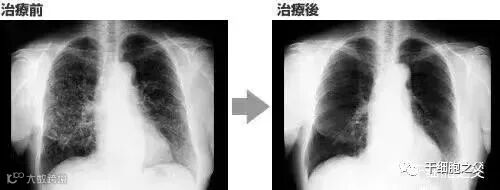

案例3:一名广泛期小细胞肺癌患者,在进行4个疗程化疗和4次高度活化NK细胞回输后,患者第一次进行治疗后的CT复查,结果显示,肿瘤缩小到了原来的1/8。而且距发病第六年的CT复查中,仍旧没有发现任何异常及复发的迹象。